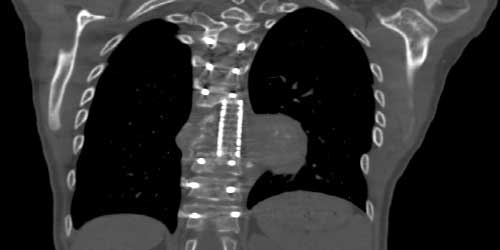

- Bilgisayarlı tomografi (BT) taraması. MRG yumuşak dokuları daha ayrıntılı gösterirken BT kemik yapıları göstermede daha üstün ve kullanışlıdır. BT taraması MRG ile kombinasyon halinde kullanılabilir. Ayrıca nereden kaynaklandığı bilinmeyen metastaz hastalarında primer odağı saptamak için akciğer, karın (batın) tomografisi çekilir. Metastatik hastalarda başka bir omurga lokalizasyonunda da lezyon olabilme ihtimalinden dolayı (%15) görüntüleme yöntemleri tüm omurgayı içerecek şekilde çekilmelidir.